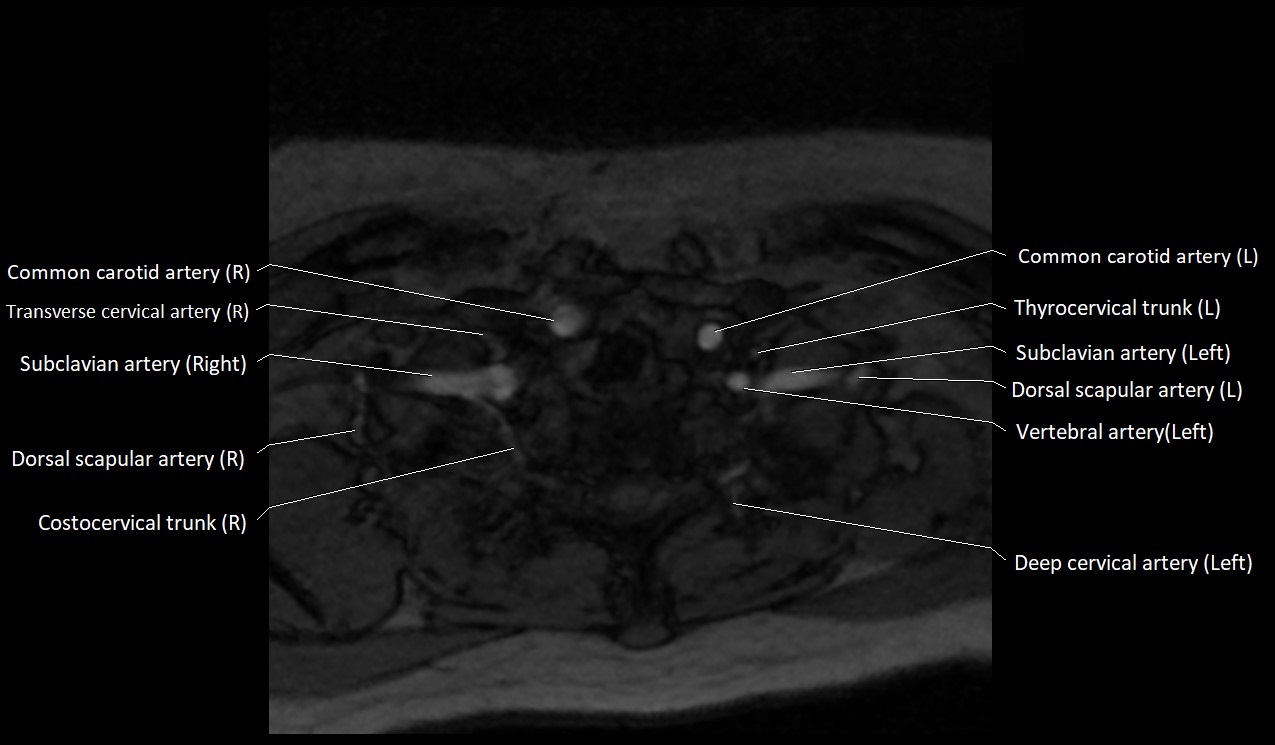

CT image

image